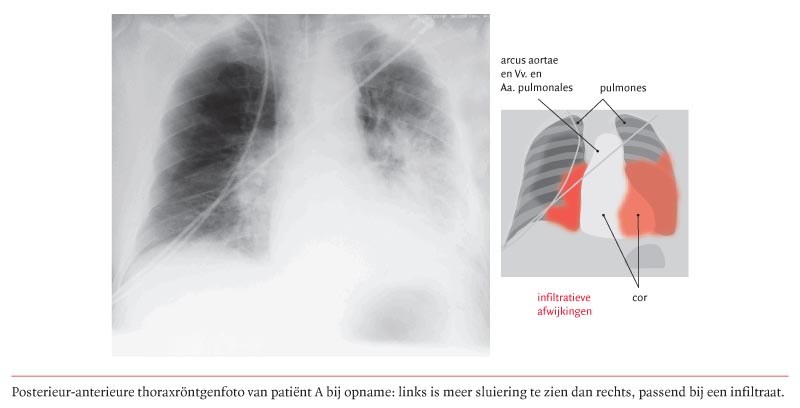

Legionella Pneumophila Atypisch Aber Auf Dem Vormarsch Swiss Medical Forum

Legionella Pneumophila Atypisch Aber Auf Dem Vormarsch Swiss Medical Forum from medicalforum.ch